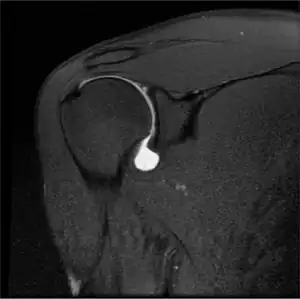

SLAP Tear

Twelve varieties of SLAP lesion have been described, with initial diagnosis by MRI or arthrography and confirmation by direct arthroscopy.[6]